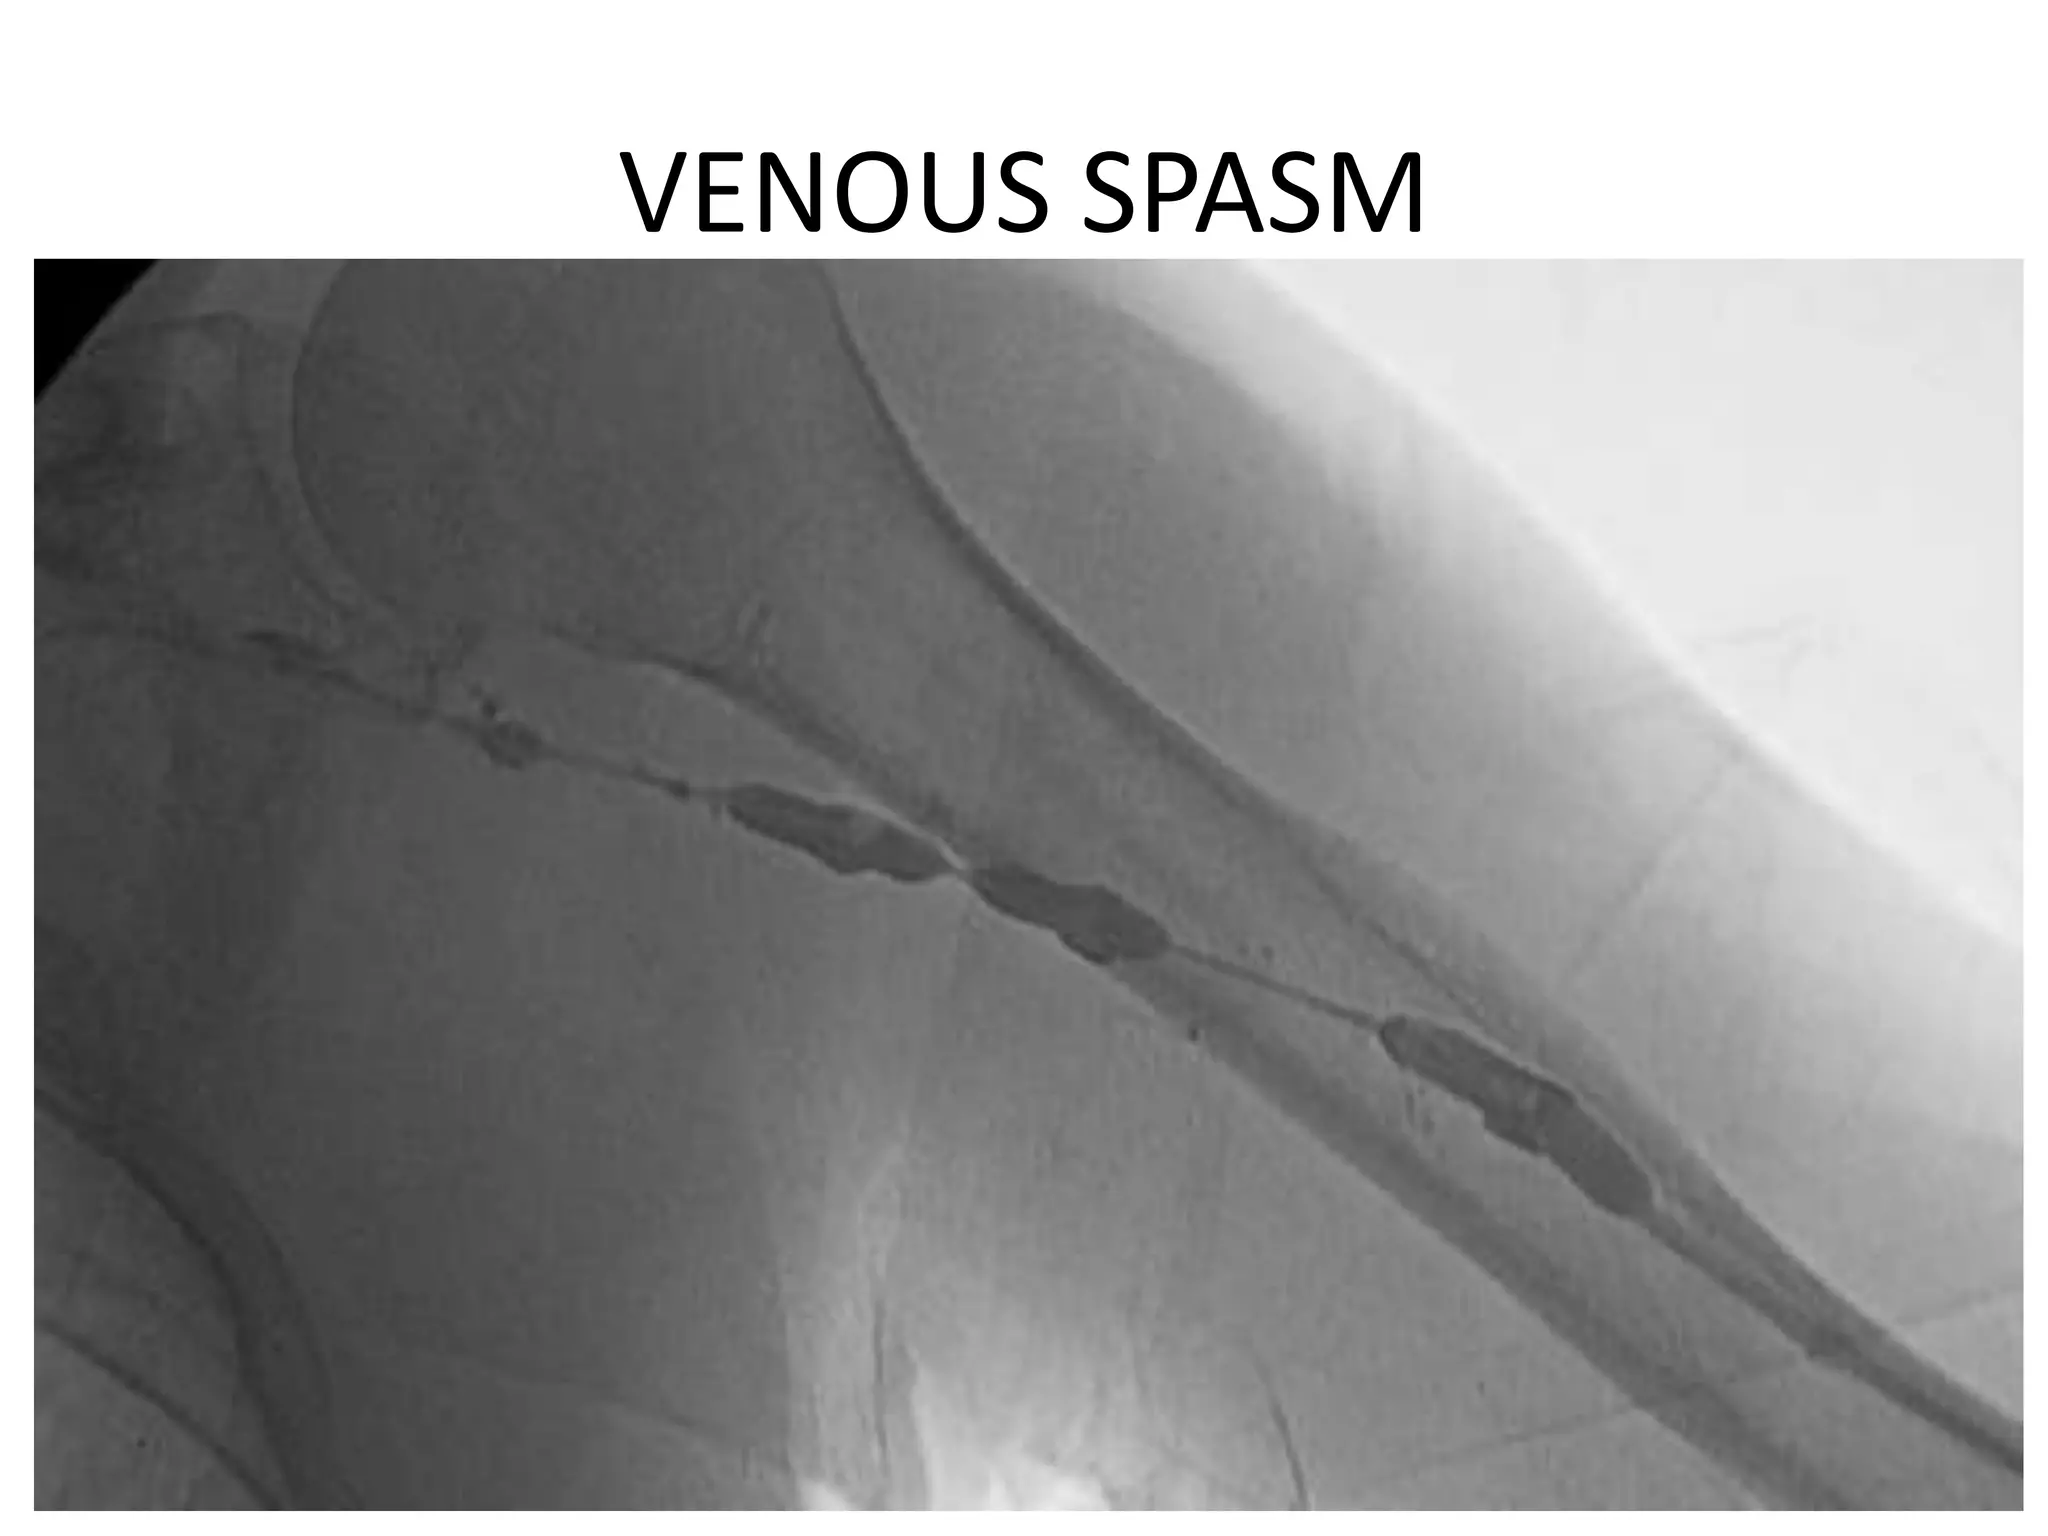

DO NOT REMOVE A PICC

1. Air Embolism

2. Syncope

3. Venous Spasm

4. Catheter Fracture

VENOUS SPASM

DO NOT REMOVEA PICC 1. Air Embolism 2. Syncope 3. Venous Spasm 4. Catheter Fracture